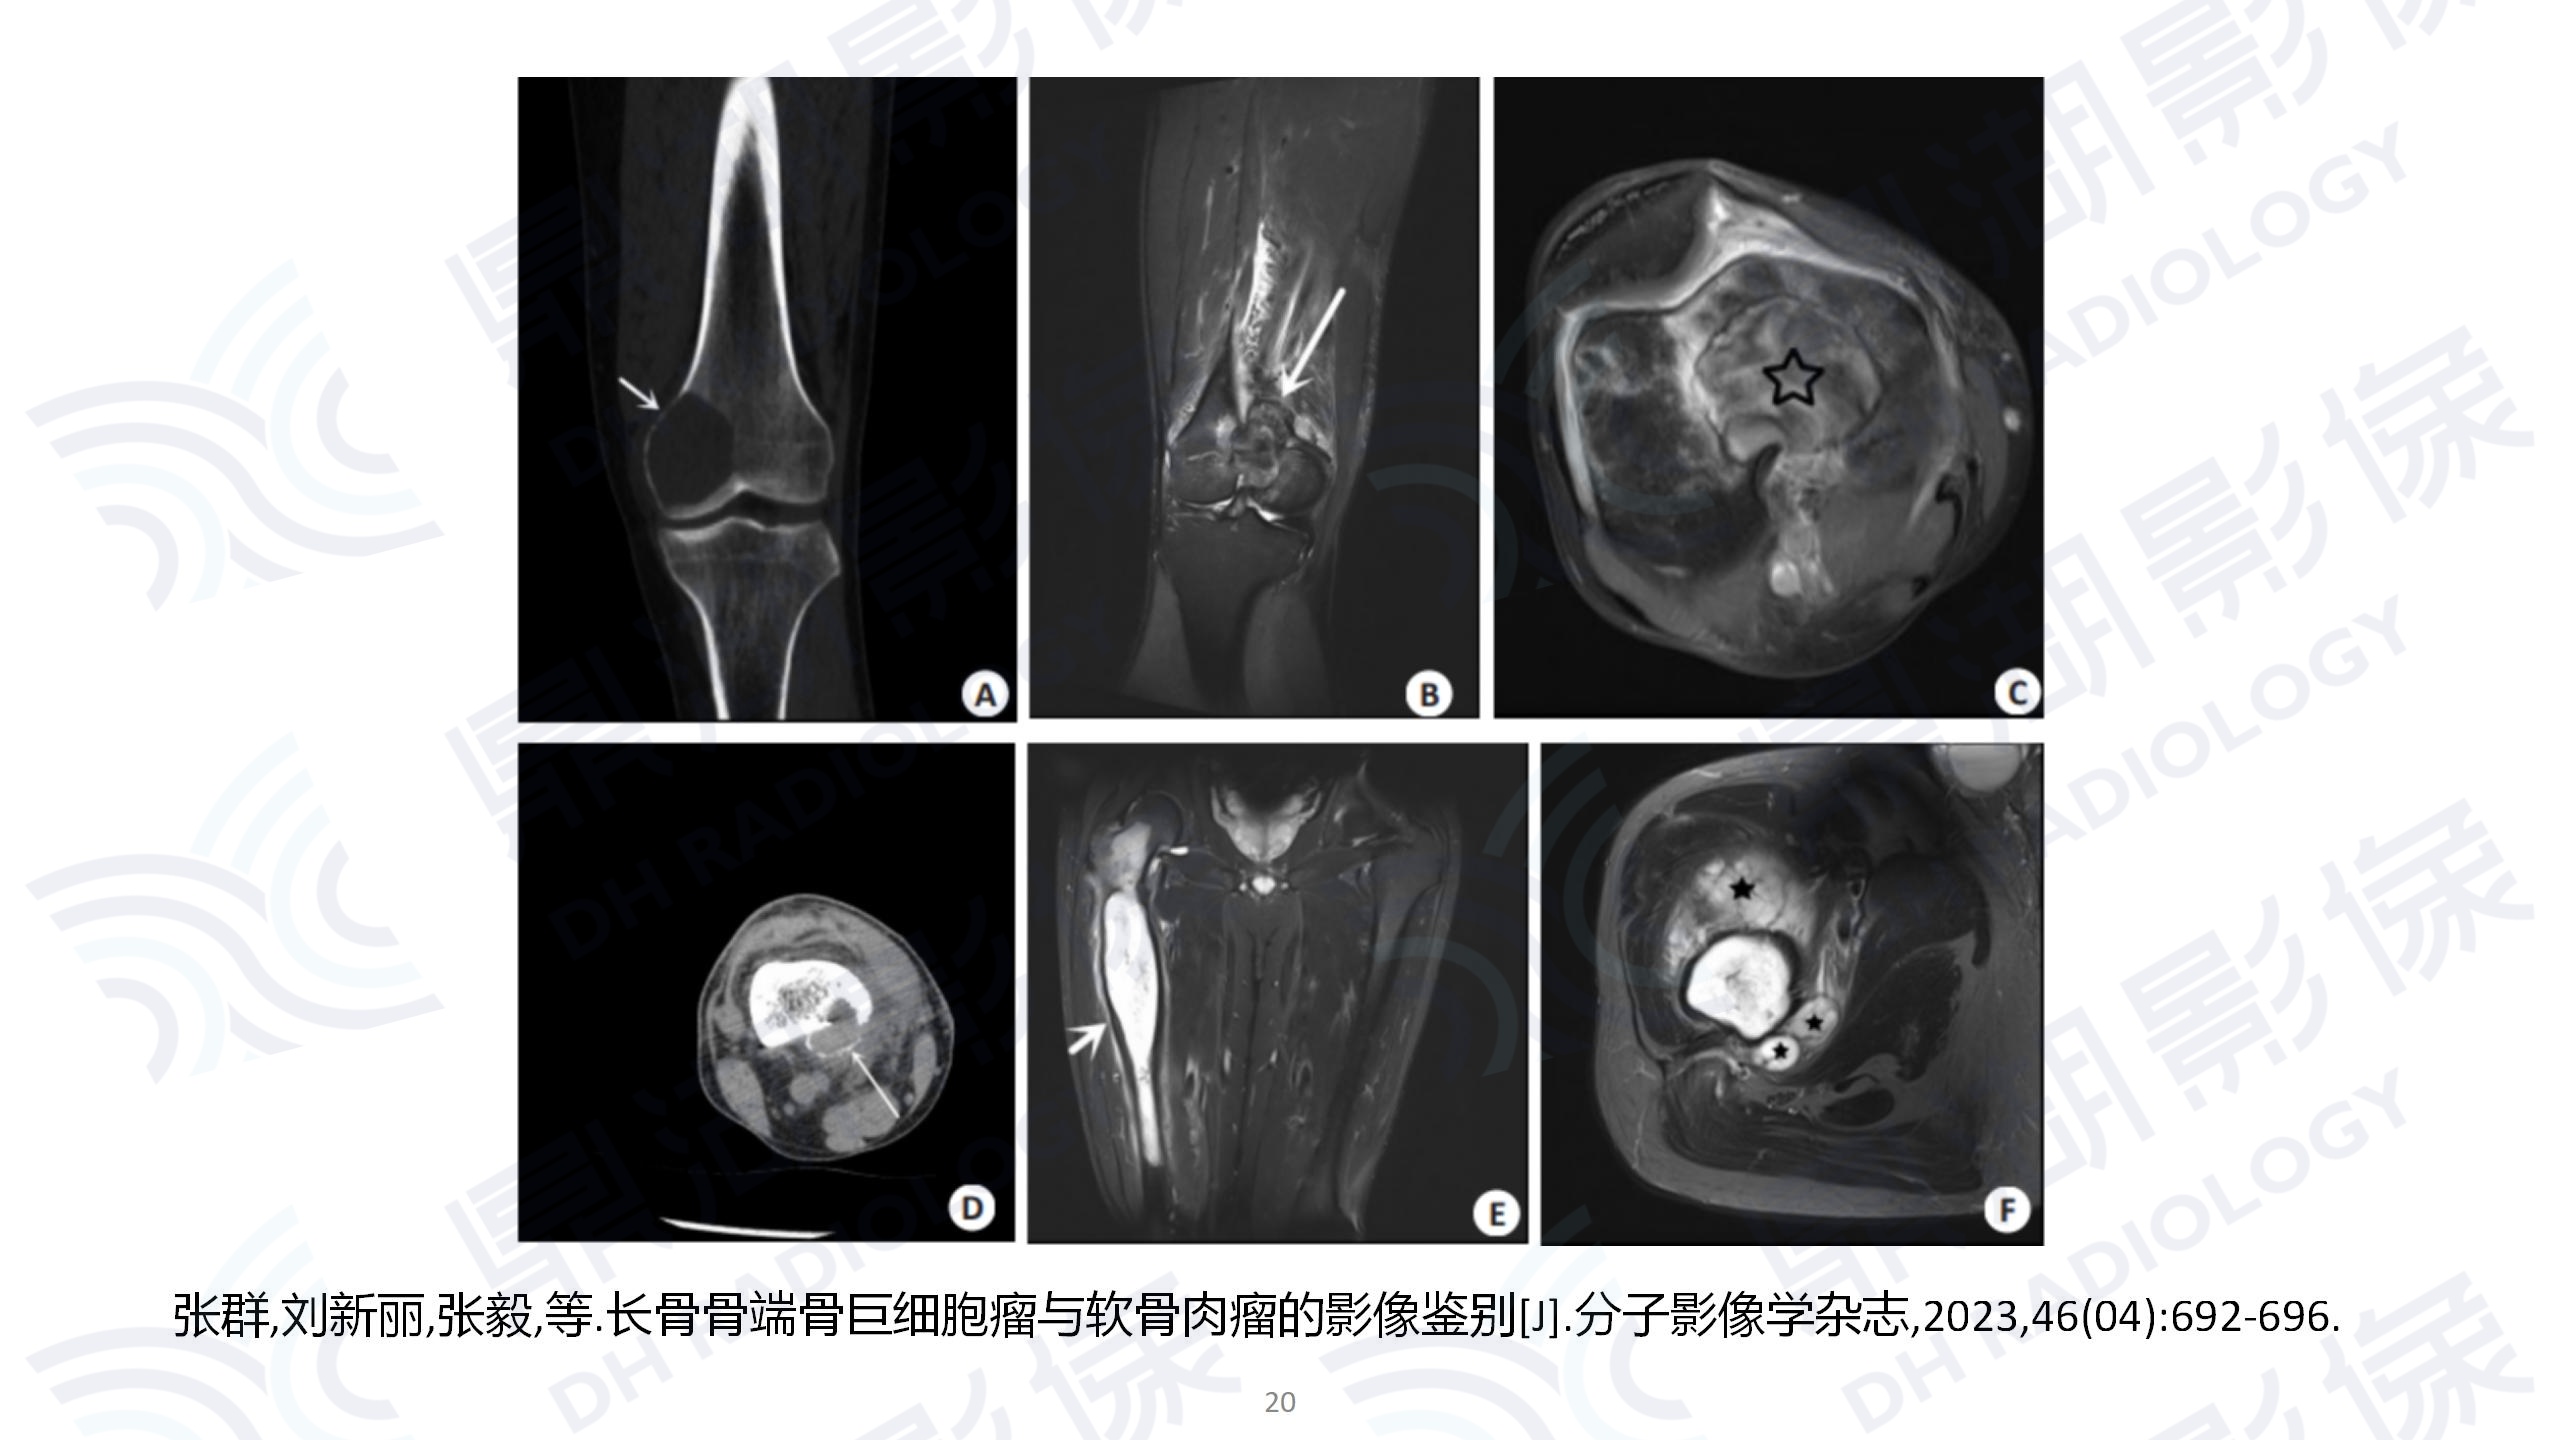

右股骨下段骨肉瘤